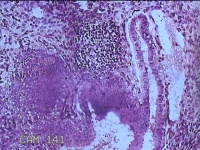

子宫腔赘生物

性别

女

年龄

33岁

临床诊断

子宫内膜息肉?子宫异常出血

一般病史

阴道流血12天。

标本名称

大体所见

灰白粉红色不规则肿物1.5x1.3x0.2cm一堆,表面糜烂。

图4